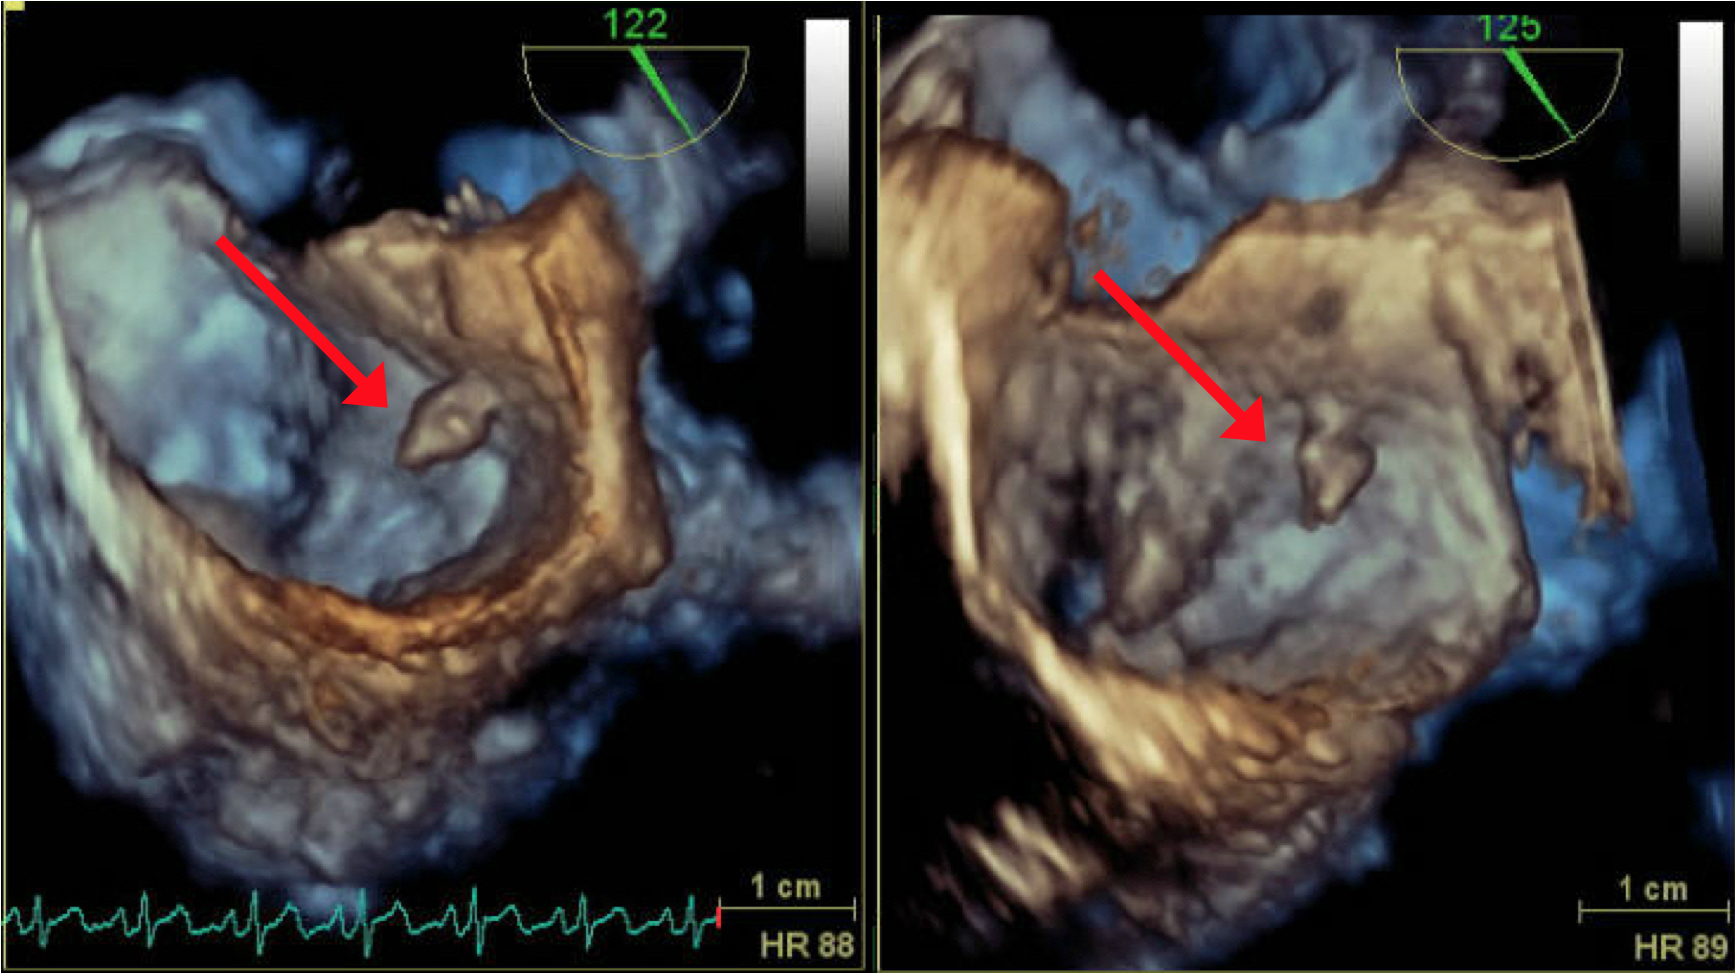

Patient was assessed with Transthoracic echocardiography (TTE) which showed mild left ventricular dysfunction (with ejection fraction of 40%) and a small mass attached to the lower interatrial septum (Figure 8). The findings were confirmed in transesophygeal echocardiography (TEE) study that described a pedunculated mass seen at the lower interatrial septum measured 0.8x0.6x0.5 cm (Figure 9 and 10) close to mitral aortic continuity. This was consistent with left atrial myxoma.

Figure 9: 3-Dimantional TEE showing the myxomatous remnant attached to the interatrial septum near the base atrial mitral leaflet.